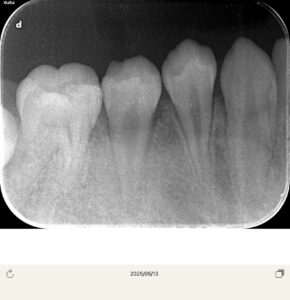

レントゲンは以前のもの

以前冷たいものが染みるということでレントゲンを撮影したが、中心結節が欠けたためと診断し、経過観察を行なっていた。

ところが7ヶ月経過して急に歯茎が腫れてきたとのことで来院

ここの真ん中の歯に中心結節があったが、そこの破折からの根管内への細菌感染とすぐに判断した。CBCTを撮影させていただき、歯根は完成しているため、再生歯内療法(REP)ではなく、MTAで根管充填をしようと計画